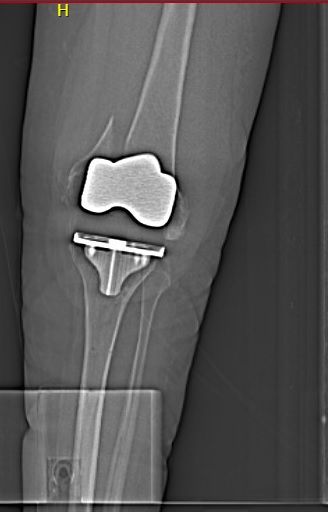

Bluegrass Orthopaedics is proud to acknowledge our latest Comeback Champion - Mrs. Kelly Fitch! A car accident in 1987 led to years of walking incorrectly, an increase in knee pain, and associated osteoarthritis which ultimately led Mrs. Fitch to decide a knee replacement surgery was necessary. An out of town physician performed the surgery, but unfortunately two weeks after the procedure Mrs. Fitch fell at home and sustained a periprosthetic fracture around her joint implant. Without realizing it, Mrs. Fitch walked on this fracture until it was diagnosed. She was sent to the ER and subsequently seen by BGO's joint specialist Dr. Kevin Denehy. The picture below shows the fracture: